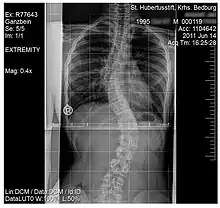

An ex-ray of a spine affected by scoliosis belonging to a 15 year old

Scoliosis, is a medical condition where a person's spine has several irregular curves that are located between the neck and the pelvis.[8] Symptoms of scoliosis in mild cases usually exhibit abnormal posture, back pain, tingling or numbness in the legs and in worse cases can exhibit breathing problems, fatigue, permanent deformities and in rare cases heart problems.[8]